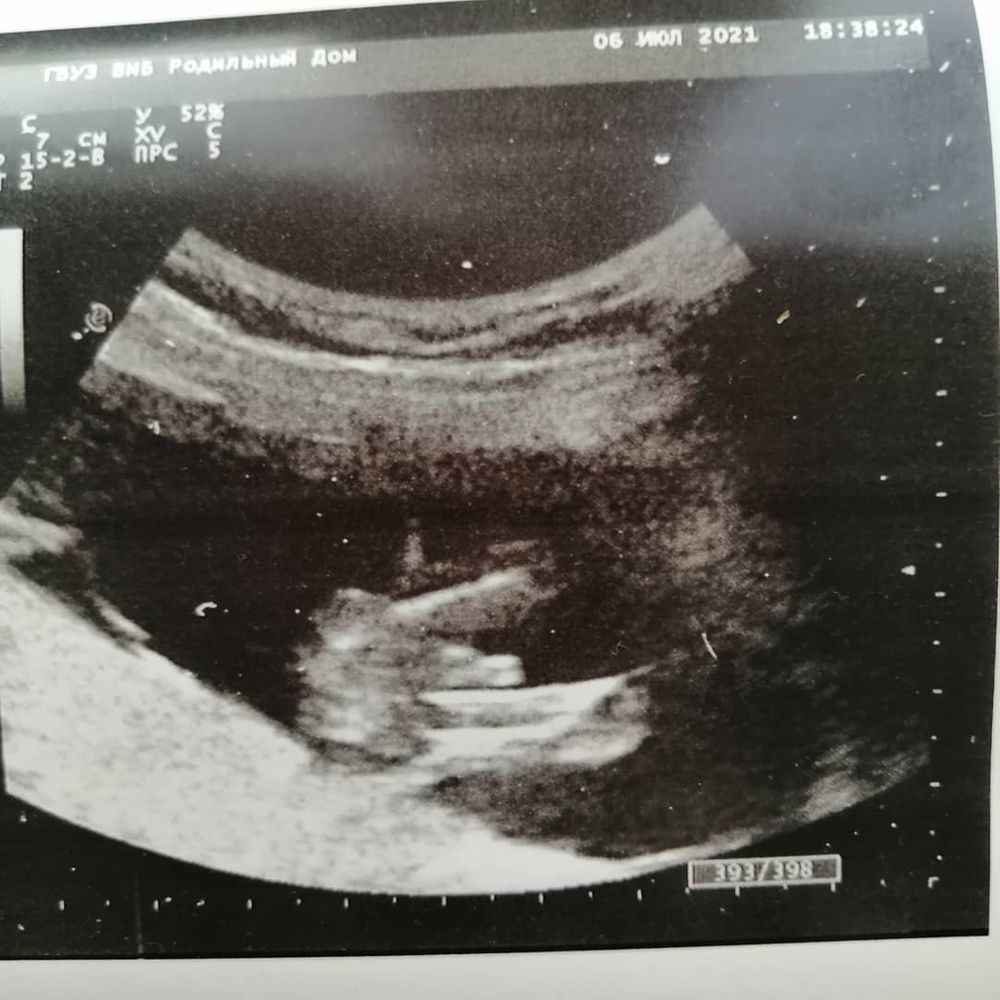

Мечты сбываются , посмотрите вот здесь, что выделено в кружок. Не похоже на девочку, а дальше там пуповина???? Изображение

Мила, да при чем тут этот кружочек, это может фото так искажать , это ж УЗИ . Там между ног всё понятно видно. У моих мужчин так же было. А у девочек там нечего такого нет, а по поводу пуповины, это всё ерунда. Мальчик у вас 💯

Мила, правда ведь похоже на девочку и пуповину? Или это просто я так вижу, потому что мечтаю о дочери?))))😂

Яна, Изображение посмотрите вот здесь, что выделено в кружок. Не похоже на девочку, а дальше там пуповина????

Кажется девчонка и пуповина , уж слишком большой перчик для 14 недель 😂

Кристина, очень надеюсь, что малышка))) Да и вообще даже не перчик, а какая-то яичковая цепь 😂🙈

Екатерина, посмотрите вот здесь, что выделено в кружок. Не похоже на девочку, а дальше там пуповина???? Изображение

Anastasia, дали снимок, сказали никак комментировать не буду, смотри сама, на втором скрининге скажу 🤷🏼‍♀️

Беременность третья, а ничего не меняется. Давайте разглядывать половой бугорок, девочки!) Девчонки подскажите???